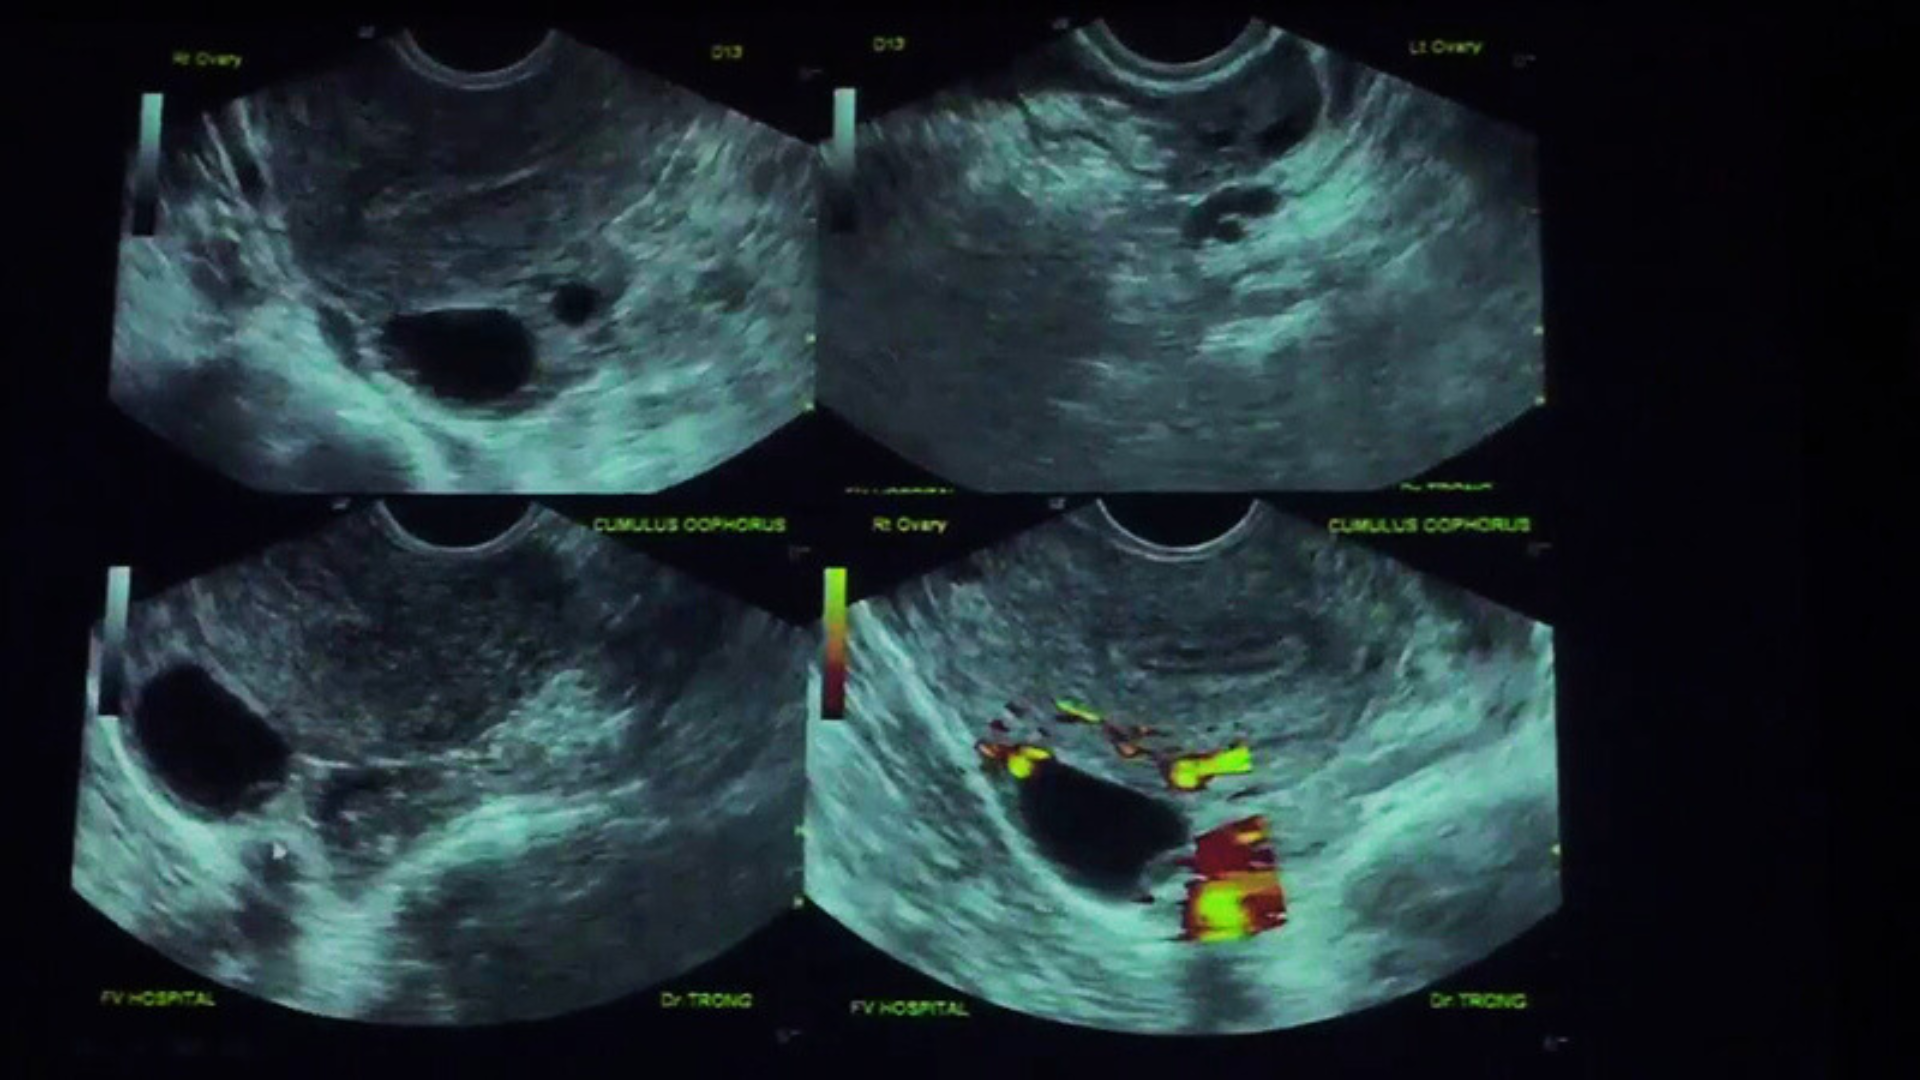

Hình ảnh siêu âm trứng sắp rụng là hình ảnh nang trứng trưởng thành được quan sát qua siêu âm khi trứng đã phát triển gần đến giai đoạn rụng trong chu kỳ kinh nguyệt. Nang trứng là cấu trúc nhỏ nằm trong buồng trứng và chứa trứng bên trong. Trong mỗi chu kỳ, một hoặc vài nang trứng sẽ phát triển, nhưng thường chỉ có một nang trội trưởng thành và giải phóng trứng.

Trên hình ảnh siêu âm, nang trứng thường xuất hiện dưới dạng một vùng tròn hoặc bầu dục chứa dịch. Khi nang trứng trưởng thành, kích thước của nó sẽ lớn hơn so với các nang trứng khác trong buồng trứng. Thành nang thường mỏng và căng, cho thấy trứng bên trong đã phát triển gần hoàn chỉnh. Những đặc điểm này giúp bác sĩ nhận biết giai đoạn mà trứng đang chuẩn bị rụng.

Trước khi trứng rụng, buồng trứng thường xuất hiện một nang trội phát triển nhanh hơn các nang còn lại. Nang trội này là nang chứa trứng có khả năng rụng trong chu kỳ.